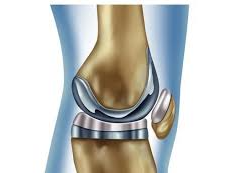

이런 경우에는 무릎 인공관절 치환술이 가장 효과적인 치료법으로 여겨지며, 수술 후에는 통증 완화 및 활동 능력 회복이 가능합니다.

일반적으로 무릎 인공관절 치환술은 한쪽 무릎 기준 300만 원에서 500만 원까지 발생할 수 있습니다. 수술 전 검사비, 입원비, 인공관절 재료비, 수술 후 재활치료까지 포함하면 금액은 더 늘어날 수 있습니다.

특히 고가의 인공관절 재료를 사용하는 경우에는 추가 비용이 발생하며, 병원의 등급 및 지역에 따라서도 수술비 차이가 큽니다. 이러한 비용은 저소득층에게 매우 부담스러울 수밖에 없습니다.